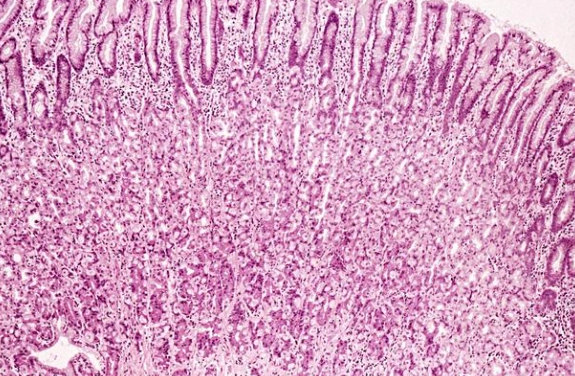

胃黏膜就是胃內壁的那層薄膜,厚度大約0.5到1.5毫米,別看它薄,功能可大了。它主要負責分泌胃酸和消化酶,幫助分解食物,同時保護胃壁不受胃酸侵蝕。你可以把它想像成胃的防護罩。

胃黏膜分成好幾層,最表層是上皮細胞,它們會不斷更新。正常情況下,胃黏膜細胞每3到5天就會更新一次,這就是為什麼胃有自我修復能力。但如果你一直傷害它,修復速度就跟不上破壞速度。